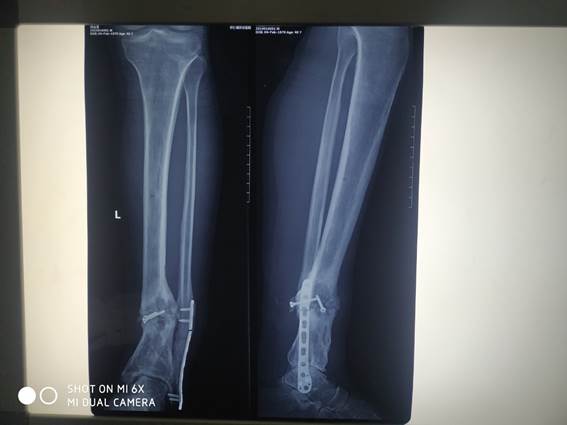

▲患者术后影像资料

此次手术难度高,用时长,操作复杂,是对医生技术及体力的双重考验。

术前,刘占宏主任及骨科团队的医护人员做好充分准备及应急方案,手术由上午十点一直进行到下午四点半,刘占宏主任和团队人员一直全心专注手术,成功为患者实施自体腓骨移植手术。